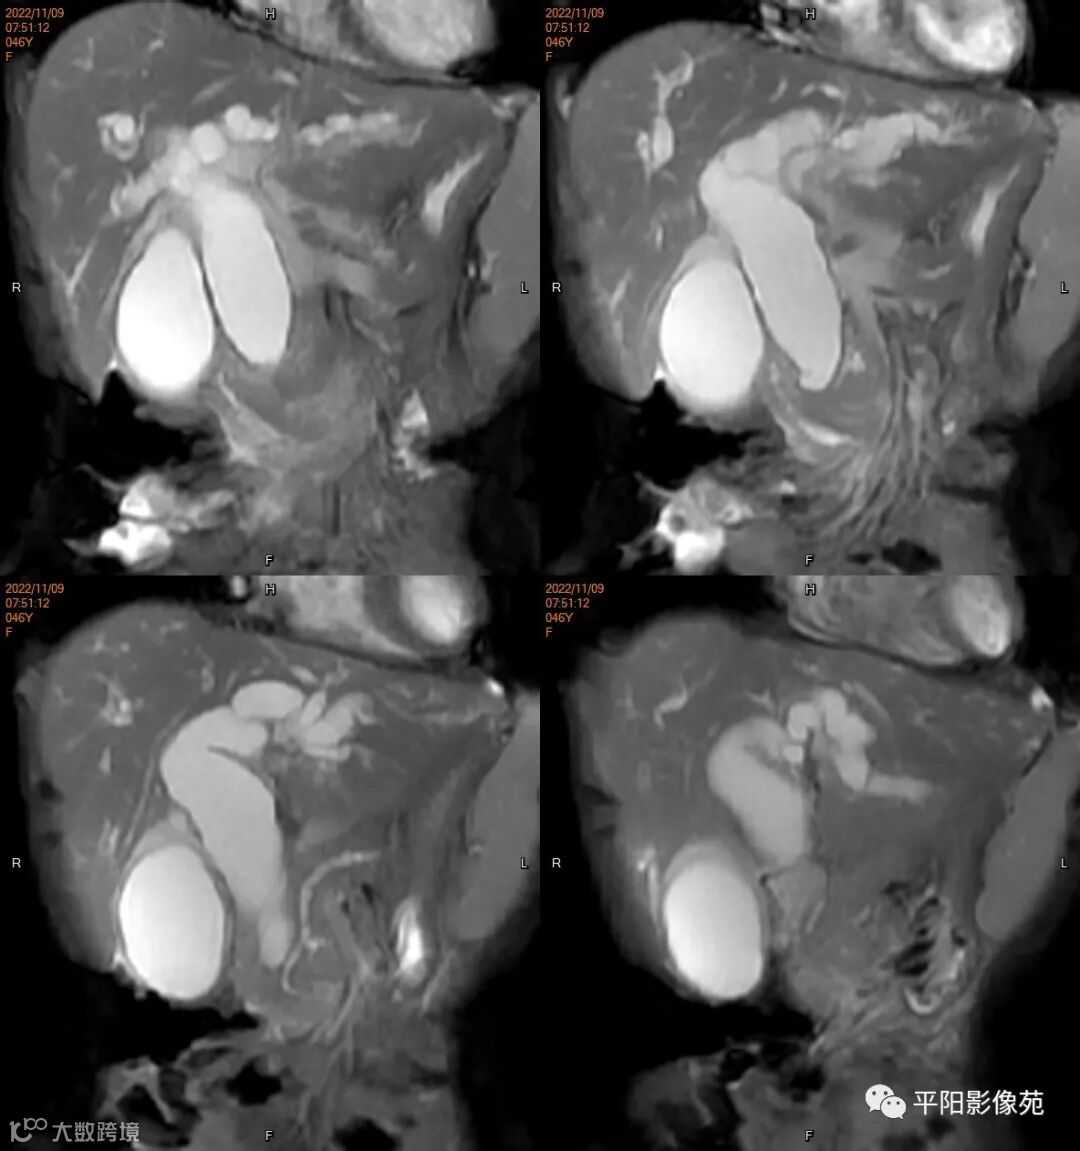

MR